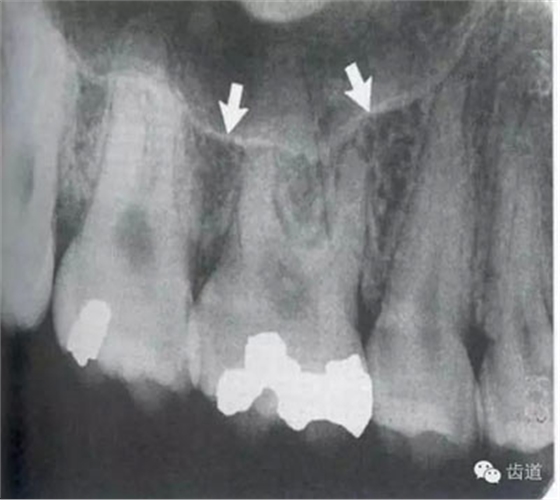

牙頸部Burnout征象:有時(shí)因投照技術(shù)問題而造成牙頸部近中或遠(yuǎn)中呈低密度影像,位于牙釉質(zhì)和牙槽嵴頂之間。